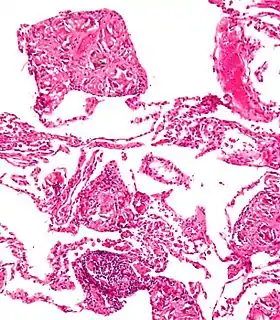

Талькоз (рос. талькоз, англ. talcosis, нім. Talkose) — хронічне захворювання легенів, яке розвивається внаслідок тривалого вдихання та відкладання в легенях пилу тальку і характеризується розвитком дифузного фіброзу. Різновид пневмоконіозу, силікатозу.